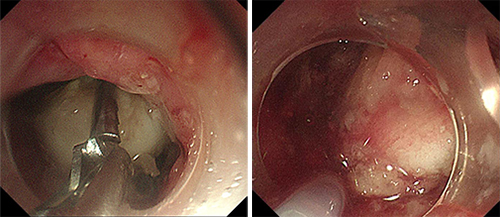

内镜手术在消化内科许洪伟主任指导下,由副主任医师李宾操作,刘华琳护士长配合操作。内镜下见异物巨大,嵌顿于食管上端致管腔扩张,异物钳无法夹持异物,更换圈套器后也无法套住异物。

尝试数分钟后,异物取出困难。李宾副主任医师当机立断,在许洪伟主任指导下更换内镜下用的胃石碎石器套取异物。胃石碎石器主要用于粉碎胃内结石,此次并不用于粉碎患者食管内的骨性异物,而是另辟蹊径,应用碎石器前端钢丝套住异物,再绷紧碎石器后端牢牢固定异物,调整牵拉方向,让患者做吞咽动作以松弛食管上段括约肌,成功拖出大小约4.0cm×2.5cm骨性异物。